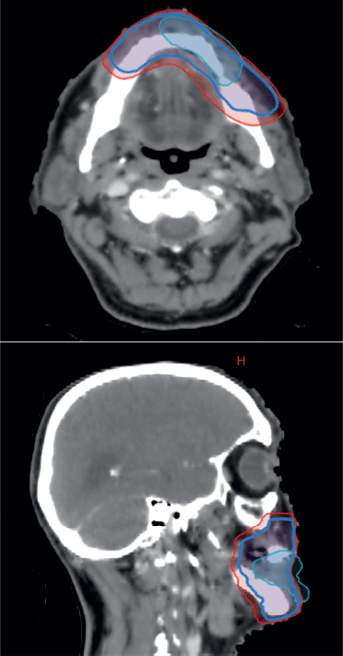

Figure 4. CT-based RT planning, representing pre-chemotherapy GTV, which has now regressed in cyan, CTV and PTV in red.

The case was revisited in the tumour board meeting, where the consensus was to proceed with consolidative radiotherapy (RT). Within 6 weeks of completing the sixth cycle of chemotherapy, the patient was scheduled for 3D conformal radiation therapy (3DCRT). Treatment planning done was involved site radiotherapy (ISRT) in which previously Pet avid site of primary lesion was contoured as pre chemo gross tumour volume (GTV) then a clinical target volume (CTV) was generated to include entire site (ISRT) in our radiation field followed by planning target volume (PTV) to incorporate set up error changes. A total dose of 3,600 cGy was delivered in 18 fractions, with 200 cGy per fraction, using 6 MeV energy and a 3 mm bolus to ensure adequate surface dose distribution (Figures 5–7).